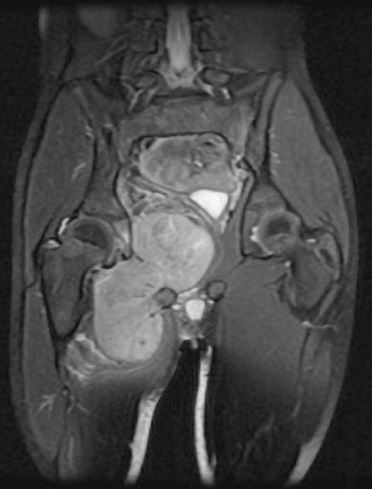

This is an MRI of the thigh region. The tumor is located in the inner right thigh (left-hand side) which is brighter than the surrounding tissues.